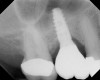

The implant is then delivered and should be well stabilized in the bone. If there is any mobility of the implant, it can either be placed a little deeper (if there is enough native bone) or the implant can be removed and the procedure aborted, in which case it would be a two-stage procedure. This should rarely occur with the tapered designed implant, even with only 2 mm of native bone. Using a bone-level platform-shifting implant (or a tissue-level designed implant) is critical, as the hard and soft tissue will establish a biologic width. If an external hex type of implant is used and the shoulder is placed at the bone level, an expected bone loss of 1.5 mm to 2 mm will occur.24 Figure 10 shows proper bone-level implant depth placement with a platform-shifting design. In this case, a 3-mm healing abutment was placed at the time of surgery to avoid a secondary uncovering surgery, but an implant-level healing abutment could have been placed instead. As can be seen, there was only about 2 mm to 3 mm of native bone height. The membrane was raised about 8 mm to 9 mm. Comparing the radiograph on the day of surgery (Figure 10) to the 6-month postoperative radiograph (Figure 11) shows no loss of native bone, as well as the positive change in appearance of the grafted bone. The 3.5-month CBCT scan (Figure 12) shows good healing of the bone with no coronal bone loss. With minimal native bone present, as in this case, the use of a non-platform-shifting or non-tissue-level implant design could be problematic. After 1.5 mm to 2 mm of crestal bone loss, an external hex designed implant could develop instability with possible implant failure. If a non-tapered implant is used and bone loss occurs during healing, migration of the implant into the sinus could potentially occur. The surgeon can use either a healing abutment or implant-level closure screw over the implant shoulder. With patients who tend to use their tongues to explore or play with the area, or if the area is under a removable partial denture, a closure screw is recommended.

A 74-year-old man presented with only about 2 mm to 3 mm of native bone below the sinus in the No. 14 position (Figure 13). The composite graft used was an approximately 50:50 mixture of DFDBA (Bio-Oss®, Geistlich Biomaterials, www.bio-oss.com) with the addition of about 40% calcium sulfate by volume (Figure 14). The implant placed (Figure 15) was a 10-mm long, rough-surfaced, platform-shifting implant (tapered 4.2 mm to 2.8 mm), and the sinus was raised about 8 mm. The postoperative radiograph taken at 4 months (Figure 16) showed some shrinkage of the graft, but no demarcation of the old sinus floor in the area.